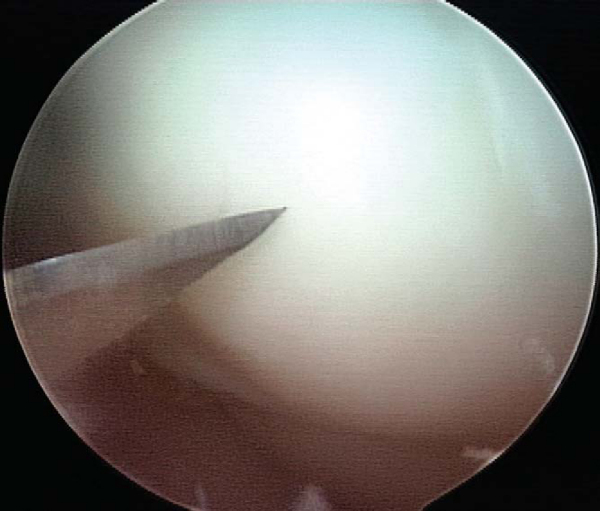

6. Implant Removal (for Nonabsorbable Implants, 3 to 4 Months after Fixation)

Use of nonabsorbable fixation typically requires a second procedure for implant removal. Implant removal can almost always be accomplished arthroscopically, regardless of whether initial fixation was obtained by open or arthroscopic technique. A diagnostic arthroscopy is performed to re-evaluate the joint and to assess healing of the lesion by arthroscopic visualization and palpation. Spinal needle localization is used to establish the appropriate vector for implant removal (

Fig. 53-13

). A noncannulated screwdriver is used to initiate screw removal because a sufficient amount of torque may be applied during this process to fracture the tip of a cannulated screwdriver. Once the screw has been backed out over several turns, a guide wire is threaded down the shaft of the screw and a cannulated screwdriver completes removal. Once the tip of the screw has been disengaged from the articular surface, the guide wire is clamped with a hemostat at a point distal to the tip of the screw to prevent loss of the screw in the joint or extra-articular soft tissue (

Fig. 53-14

). The lesion should then be probed for stability and the knee brought through a cycle of flexion-extension (

Fig. 53-15

).

Figure 53-13   |